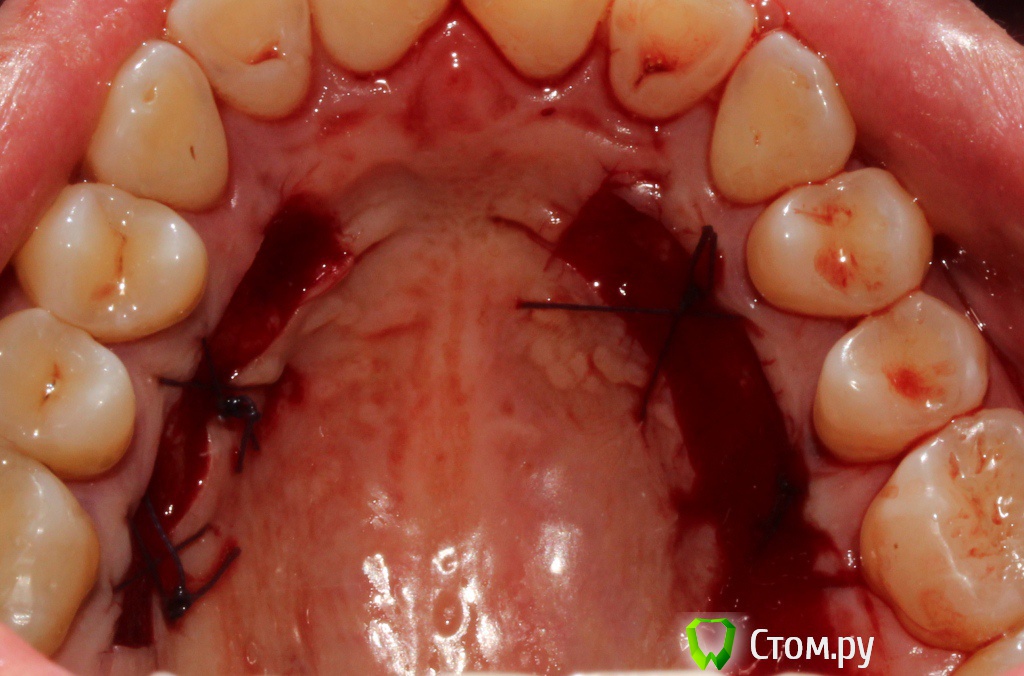

Популярный пост zzkz Опубликовано 18 сентября, 2014 Популярный пост Поделиться Опубликовано 18 сентября, 2014 (изменено) Жалобы эстетические и сильная чувствительность Рецессия от 34 до 44 Подготовка поверхности корней только скэйлинг СДТ с 2-х сторонНа небе каппа Ушивание пролен 6-0 2 недели после Чувствительности нет на сегондя. Ждать ли еще убыли или прироста? Сосочек закрыл "черный треугольник". Не уйдет ли? Изменено 18 сентября, 2014 пользователем zzkz 33 Ссылка на комментарий

NickN Опубликовано 18 сентября, 2014 Поделиться Опубликовано 18 сентября, 2014 Классный результат! Небо с двух сторон ободрали? Ссылка на комментарий

zzkz Опубликовано 19 сентября, 2014 Автор Поделиться Опубликовано 19 сентября, 2014 по шейкам мне кажется чуть выравняется. Про сосочки не знаю. Мне очень понравилась Ваша работа. очень вкусно +1 шейки выровняются.Сделайте реколл через 3 и 6 месяцев посмотрим как дозреет.Работа классная!! Классный результат!Небо с двух сторон ободрали?Спасибо. Да конечно, реколл зафиксирую. Небо начал шить, потом подумал - ааа нафиг, все равно под каппу Ссылка на комментарий